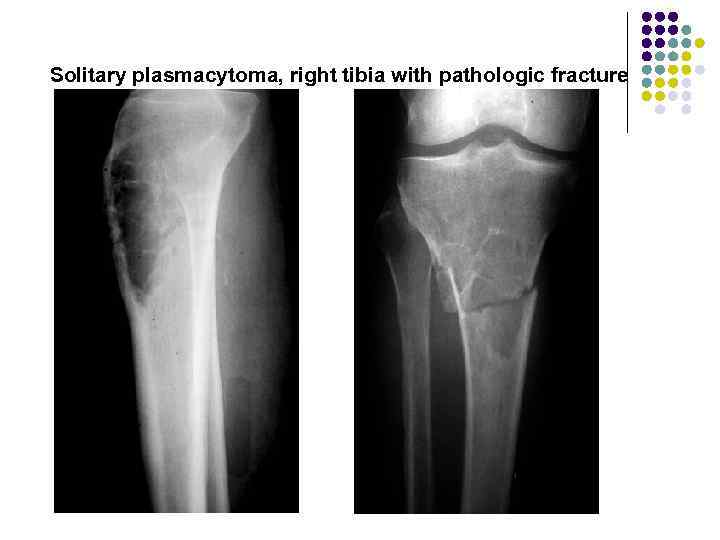

Solitary plasmacytoma, right tibia with pathologic fracture